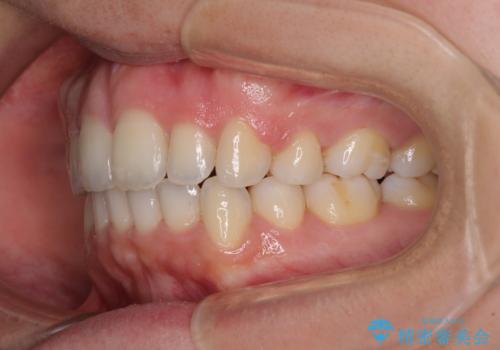

- 前歯のデコボコと口元の突出感を気にして来院された患者様です。

上下左右第一小臼歯4本を抜歯し、ワイヤー装置にて口元を引っ込めるよう矯正治療を行うこととしました。

叢生が強かったため、口元の突出感の改善には限界がありましたが、横側からも口元が引っ込んだ感じが分かるほど改善されました。